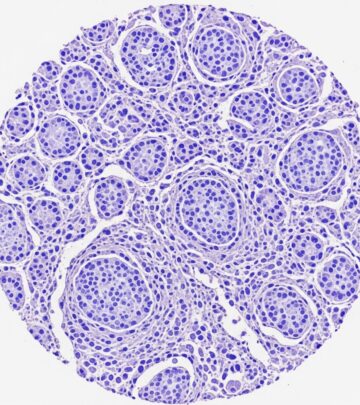

Fibrofolliculomas in Birt-Hogg-Dubé Syndrome Images